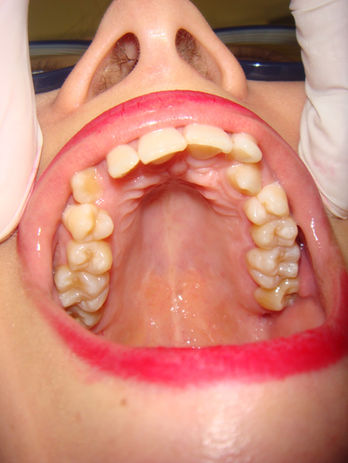

Grazie al microscopio, infatti, si riesce in modo ottimale a ristabilire l'anatomia degli elementi dentali.